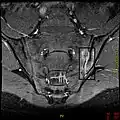

If these criteria still do not give a compelling diagnosis magnetic resonance imaging (MRI) may be useful.[22][24] MRI can show inflammation of the sacroiliac joint.

T1-weighted MRI with fat suppression after administration of gadolinium contrast showing sacroiliitis in a person with ankylosing spondylitis